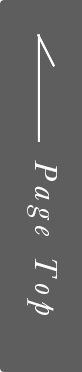

親知らずの抜歯は歯科治療の一種ですが、水平埋伏(横に生えている場合)などの「難症例」は、どこの歯科院でも対応しているわけではなく、大学病院へ紹介されるケースが多いです。

通常は「2次元」で撮影するレントゲンを使用して診断を行いますが、当院では「3次元」での撮影が可能なCTを用いてより詳細な診断を行います。

2次元と3次元では「見える範囲」が異なります。

下の画像は他の治療のケースですが、同じ部位を2次元レントゲン(左)、3次元のCT(右)で撮影したものです。

丸がついている部分が問題の生じている部分で、3次元ではしっかり黒い影が見えますが、2次元ではそれが確認できません。

簡単にまとめると、2次元レントゲンだけでは「問題が見落とされる」可能性があるということです。

歯科医療では、「見える」「見えない」が大きな違いを生みます。

当院では、しっかりとした視野を提供する3次元のCT装置を使って診断を行っています。

主訴 | 親知らずを抜きたい |

|---|---|

治療期間 | 3週間 |

治療費 | 20,000円 |

治療内容 | CT撮影、上下左右8抜歯 |

治療のリスク | 下歯槽神経麻痺、腫脹、疼痛 |